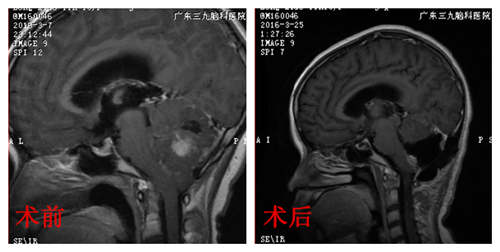

影像学资料显示,婷婷是后颅窝占位性病变,考虑髓母细胞瘤的可能性大,应尽快手术治疗,解除这个肿瘤对婷婷生命造成的危害。确定手术方案后,小儿神经外科在显微镜下为婷婷进行肿瘤切除手术,并完好地保护了婷婷的重要脑组织部分。术后,婷婷辅以放化疗治疗,头痛、呕吐症状消失。

术后病理报告提示:髓母细胞瘤。